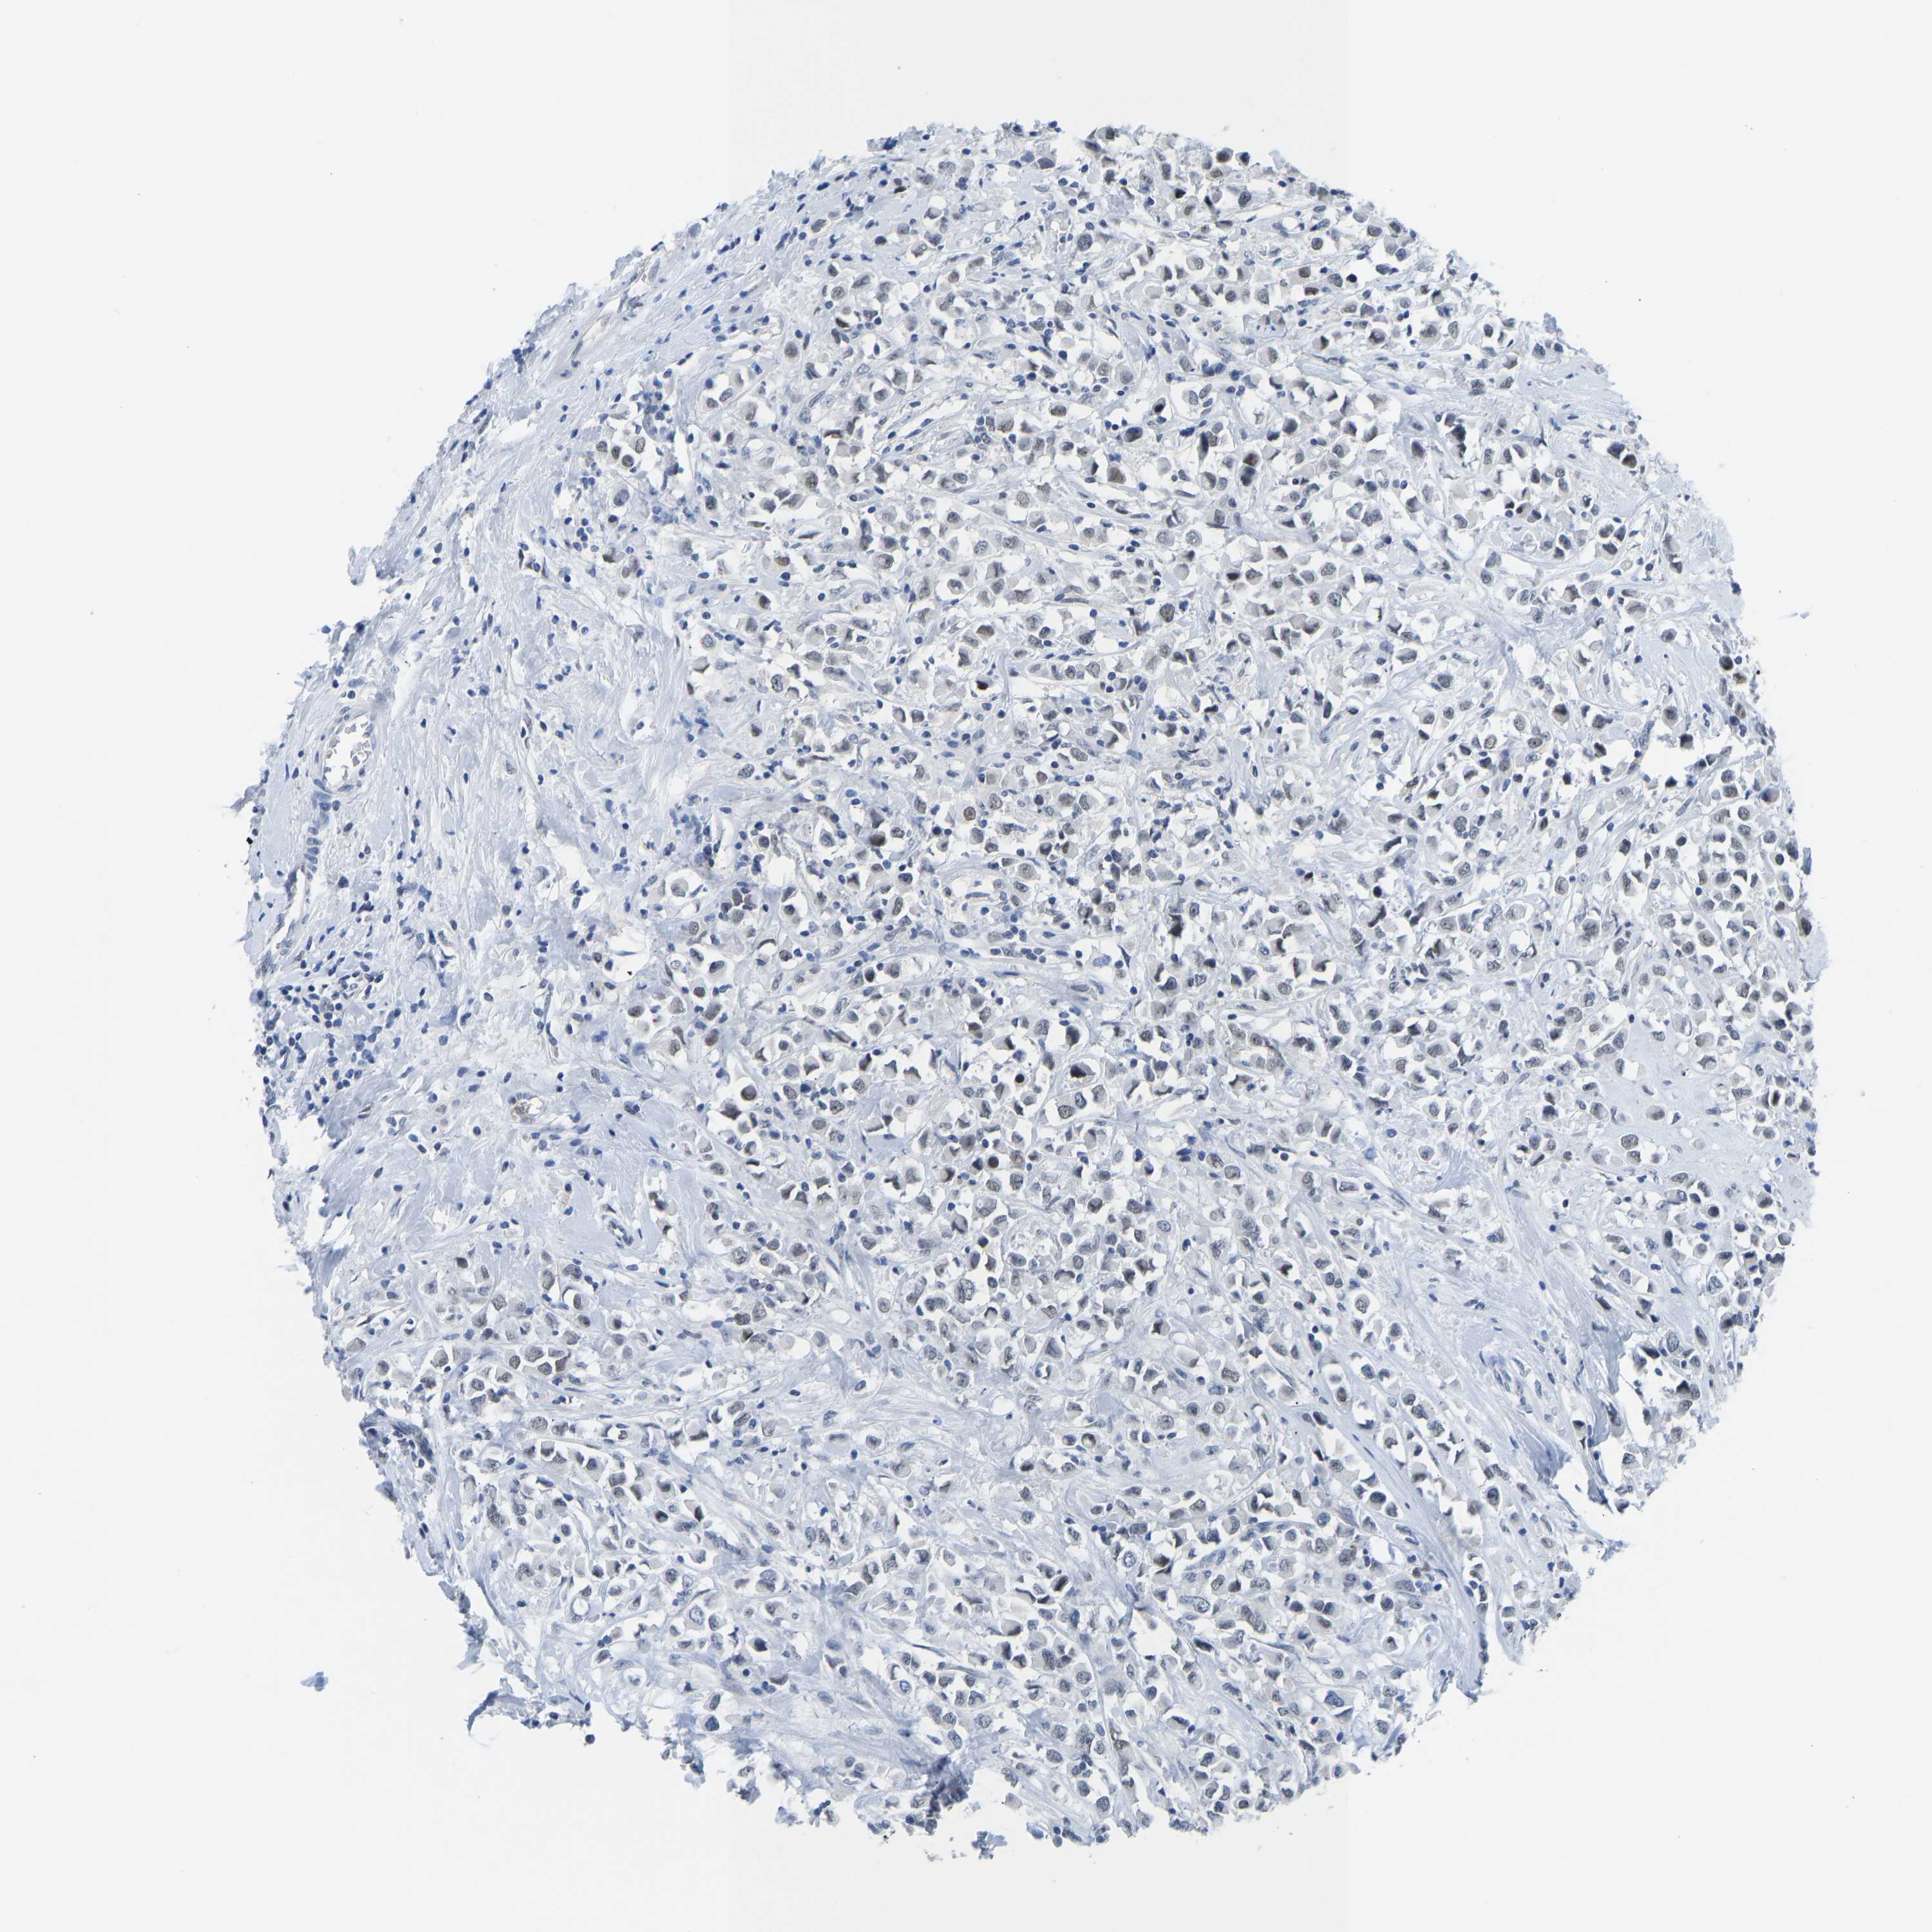

CANCER BREAST CANCER Show tissue menu

BRCA TCGA BRCA VALIDATION PROTEIN EXPRESSION